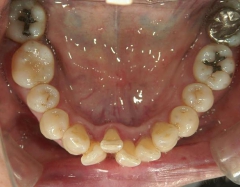

矯正歯科 治療前矯正歯科 治療前

矯正歯科 治療前

矯正_灰色.pngno.12_5333_治療前_下.jpg矯正_灰色.png